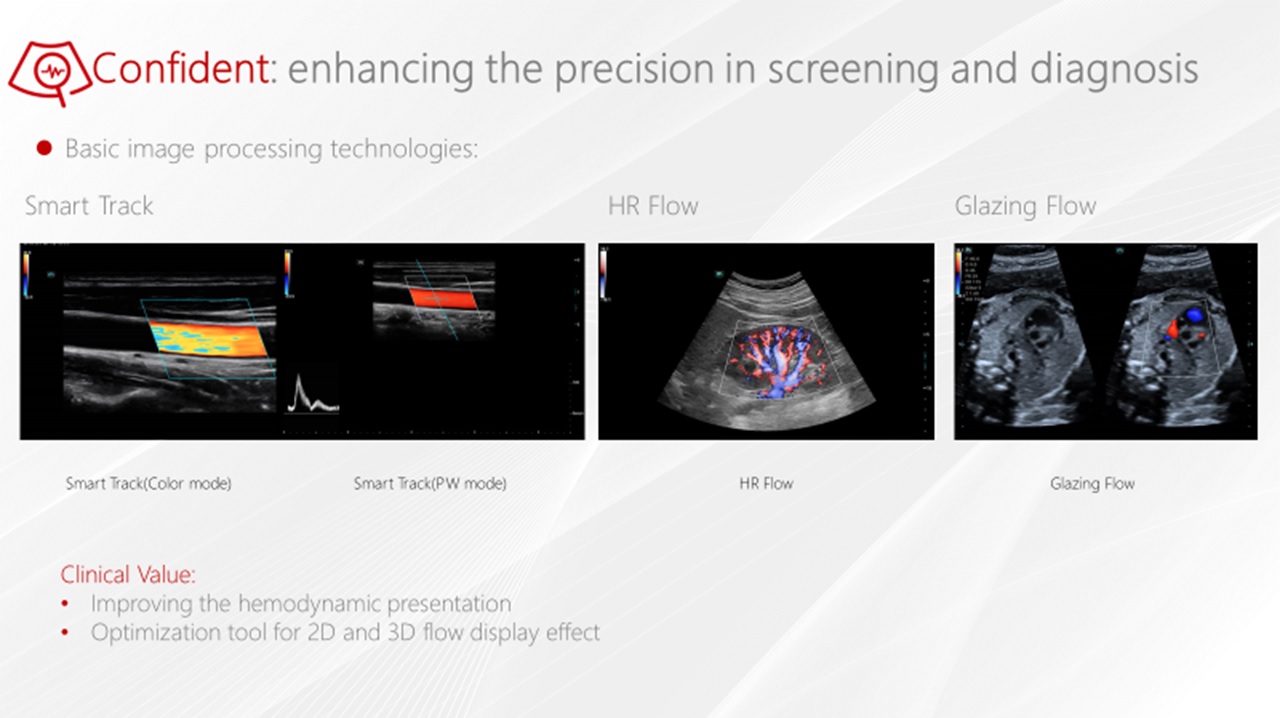

- HR Flow, Echo Boost

Smart Track

Unikátne sledovanie cievy, optimalizácia dopplerovského okna. Nastavenie Color/Power/PW pozíciu ROI, uhol steeringu atď... Výrazné zjednodušenie vyšetrovania ciev.

Glazing Flow : 3D zobrazenie ciev : Úplne nový spôsob zobrazenia prietoku krvi pomocou 3D vizualizácie

Glazing Flow : Nový spôsob demonštrácie prietoku krvi pomocou 3D vizualizácie. Špeciálne efekty nasnímaného svetla pri zobrazení rýchlosti prúdenia. K dispozícii s farebným a power dopplerom. Intuitívne a dynamické zobrazenie prietoku krvi vo vysokom rozlíšení a jasnosti, špeciálne pre tenké a prekrývajúce sa cievy.

Glazing Flow : Nový spôsob demonštrácie prietoku krvi pomocou 3D vizualizácie. Špeciálne efekty nasnímaného svetla pri zobrazení rýchlosti prúdenia. K dispozícii s farebným a power dopplerom. Intuitívne a dynamické zobrazenie prietoku krvi vo vysokom rozlíšení a jasnosti, špeciálne pre tenké a prekrývajúce sa cievy.